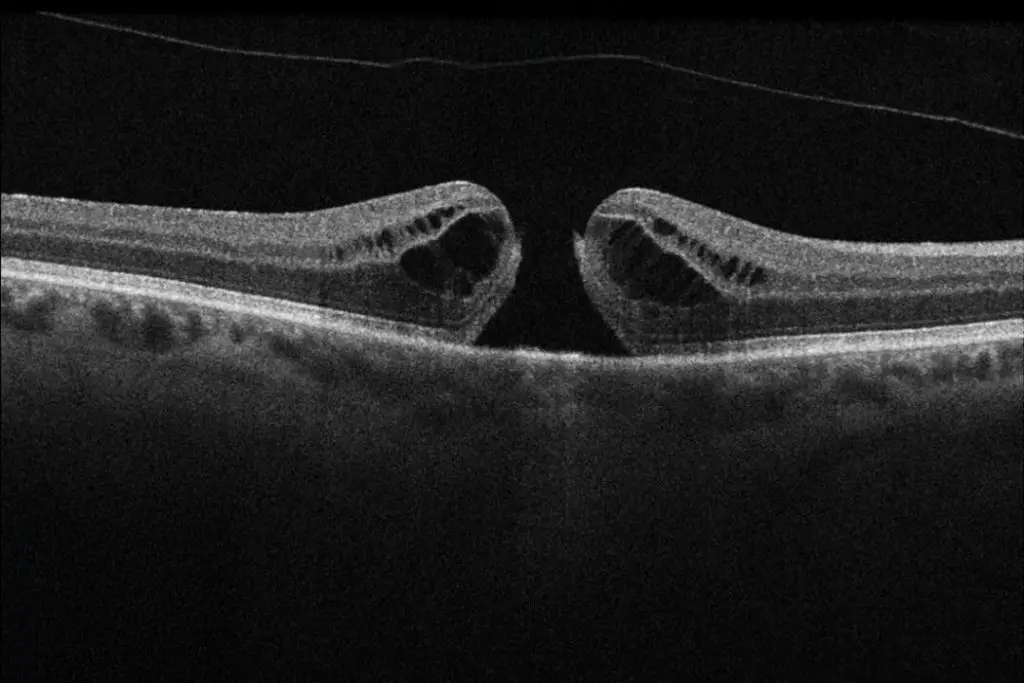

Optische Kohärenztomographie

Die Optische Kohärenztomographie (OCT) ist ein hochauflösendes, nicht-invasives Bildgebungsverfahren, das zur detaillierten Untersuchung der Netzhaut, des Sehnervs und der vorderen Augenabschnitte eingesetzt wird.

Sie basiert auf Lichtwelleninterferometrie und ermöglicht die Schicht-für-Schicht-Darstellung der Netzhaut in mikroskopischer Detailgenauigkeit.

Funktionen und Anwendungen der OCT:

• Netzhautdiagnostik: Erkennung und Verlaufskontrolle von Makuladegeneration (AMD), diabetischer Retinopathie, Makulaödem, Makulaforamen u. a.

• Beurteilung von Netzhautablösungen und epiretinalen Membranen.

• Operationsplanung und Nachkontrolle: Bewertung der Netzhaut vor und nach intravitrealen Injektionen (IVOM), Katarakt-OP oder vitreoretinalen Eingriffen.

Makulaloch – Ein Loch in der Sehmitte

Ein Makulaloch ist ein Defekt in der Netzhautmitte, der das zentrale Sehen stark beeinträchtigt. Es entsteht, wenn sich der Glaskörper im Auge altersbedingt verändert und an der Makula zieht.

Ein Makulaloch heilt meist nicht von selbst. Die einzige wirksame Therapie ist eine Operation (Vitrektomie mit Gasfüllung), bei der der Glaskörper entfernt und das Loch durch ein Gas oder Öl geschlossen wird. Nach der OP kann sich das Sehvermögen deutlich verbessern.

Unser Fazit

Makulaerkrankungen wie epiretinale Gliose oder Makulalöcher können das zentrale Sehen erheblich beeinträchtigen. Eine frühe Diagnose durch eine Augenuntersuchung (z. B. OCT) hilft, rechtzeitig eine geeignete Behandlung einzuleiten und das Sehvermögen zu erhalten. Bei plötzlichen Sehverschlechterungen sollte immer ein Augenarzt aufgesucht werden!